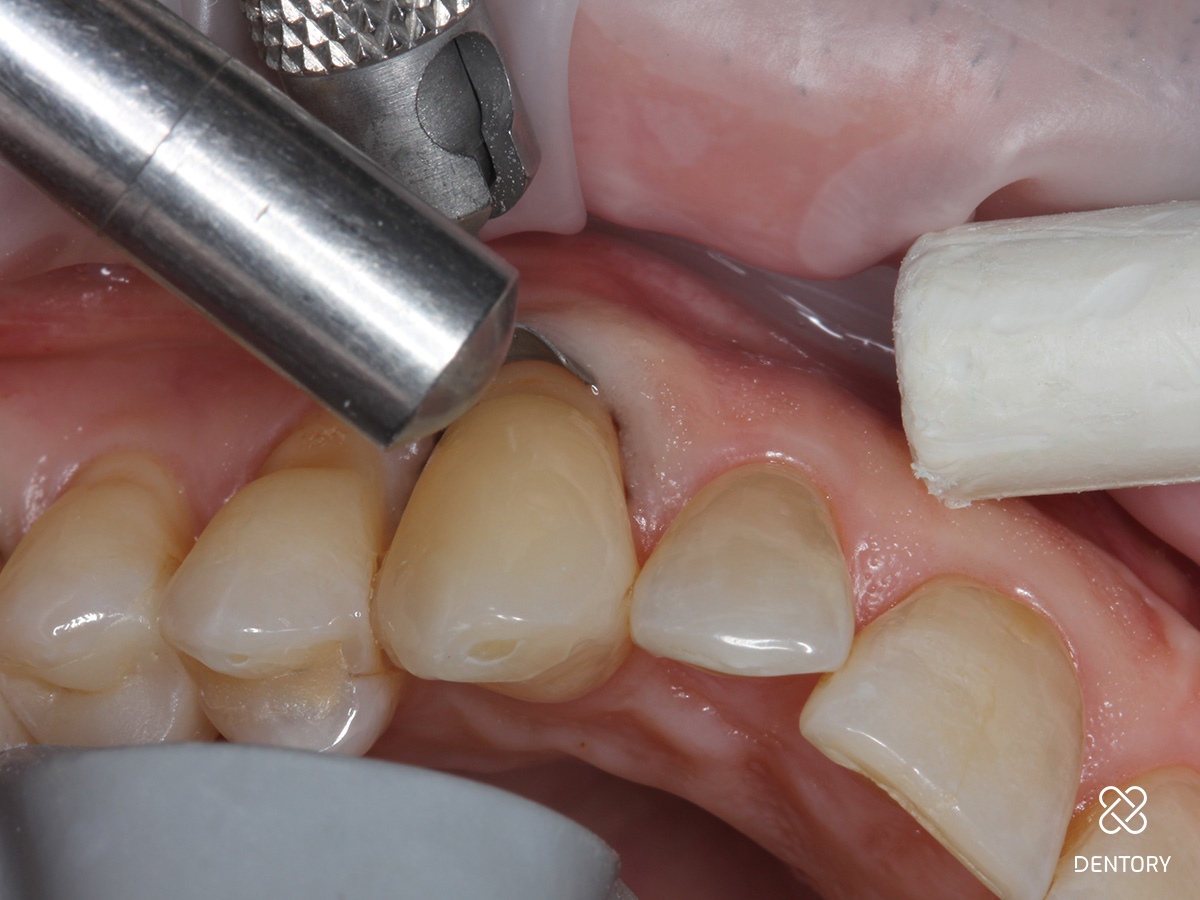

Abbildung 3

Zunächst Beläge und Biofilm sauber entfernen. Um eine Blutung des umgebenden Gewebes zu verhindern, wird ein Gingiva Schutzhalter angelegt. Das Instrument lässt sich schnell individuell anpassen und dem Zahnhals entsprechend formen. Die Gingiva wird leicht nach unten geschoben, um einen perfekten Sitz des Instrumentes zu garantieren.